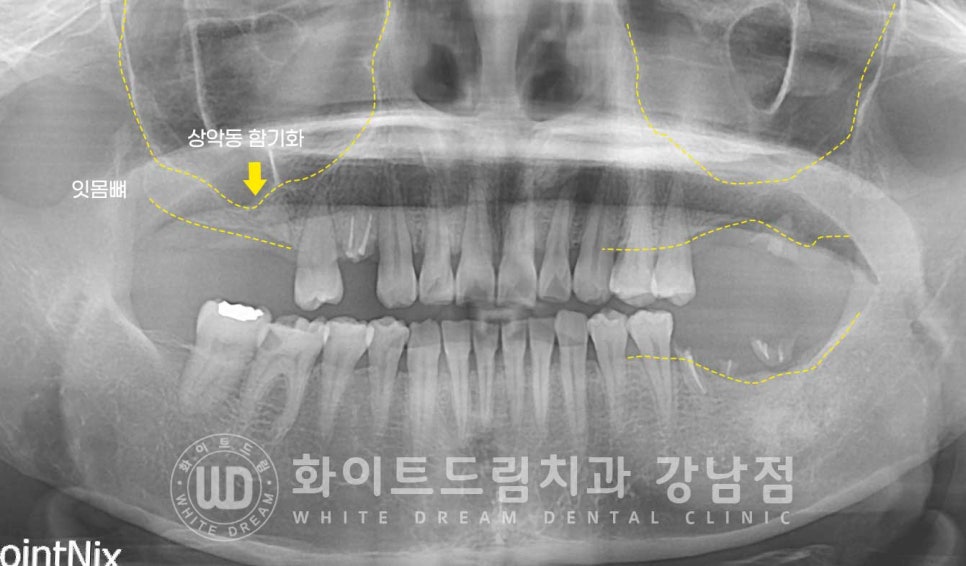

환자분의 초진 구내 상태입니다.

16,17번 치아는 상실된 상태이고

14, 27, 36,37번 치아가 뿌리만 남아있는 상태입니다.

환자분도 염증으로 잇몸뼈의 소실이 발생했기에 모든 부위는 뼈이식을 동반해야 했고

이 중에서 상악 16,17번 치아 부위는

치아를 발치한지 오랜 시간이 지나 잇몸뼈의 함몰과 상악동의 함기화가

일어나 임플란트를 식립하기에는 잇몸뼈의 양이 많이 모자란 상태였습니다.

이럴 때 상악동을 살짝 들어 올린 후 모자란 뼈를 형성하는 방법이

바로 '상악동 거상술'이랍니다.

상악동의 얇은 막을 들어 올려, 그 빈 공간에 뼈이식재를 넣어 새로운 뼈를 형성해 주는 방법으로

환자분의 경우 많은 양의 잇몸뼈가 필요했기에

볼 쪽 잇몸뼈에 작은 창문을 내어 진행하는 lateral, 측방 접근법을 동반하게 되었습니다.

▲ 상악동 거상술 & 임플란트 수술 후 (23.03.07)